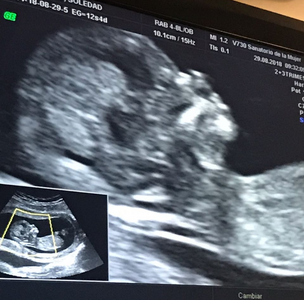

Entonces hicimos las primeras ecografias, realmente sorprendentes. Hasta le dije a la ecografa si no se parecía a un extraterrestre. Aunque uno ya lo sabe, después parece mágico, sin explicación. Y escuchamos su corazón y empezamos a preguntarnos que sería. Y es un varón. y creció la panza y entonces mi vida se dio vuelta como un panqueque.